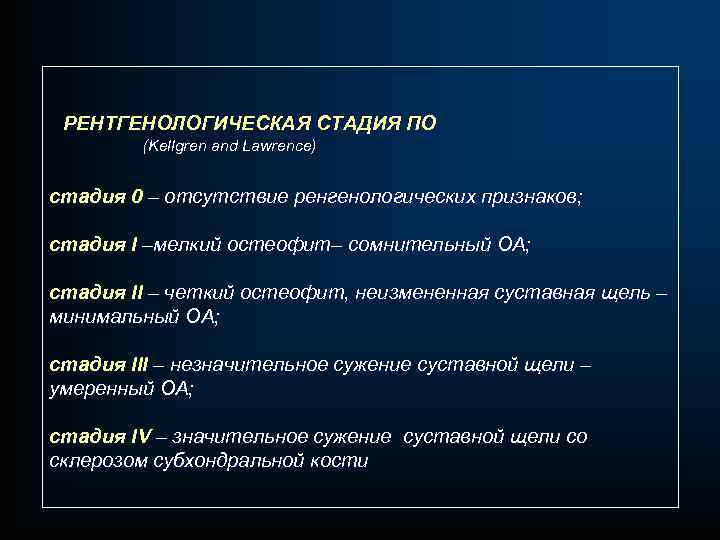

РЕНТГЕНОЛОГИЧЕСКАЯ СТАДИЯ ПО (Kellgren and Lawrence) стадия 0 – отсутствие ренгенологических признаков; стадия I –мелкий остеофит– сомнительный ОА; стадия II – четкий остеофит, неизмененная суставная щель – минимальный ОА; стадия III – незначительное сужение суставной щели – умеренный ОА; стадия IV – значительное сужение суставной щели со склерозом субхондральной кости

РЕНТГЕНОЛОГИЧЕСКАЯ СТАДИЯ ПО (Kellgren and Lawrence) стадия 0 – отсутствие ренгенологических признаков; стадия I –мелкий остеофит– сомнительный ОА; стадия II – четкий остеофит, неизмененная суставная щель – минимальный ОА; стадия III – незначительное сужение суставной щели – умеренный ОА; стадия IV – значительное сужение суставной щели со склерозом субхондральной кости